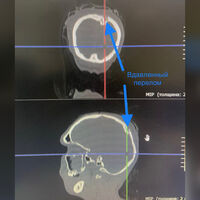

Мужчина поступил в больницу на скорой с множественными переломами, вдавленными переломами теменной кости черепа, повреждением крупных сосудов мозга и обширной кровопотерей. Ему сделали переливание крови, после чего медики приступили к операции.

«Врачи освободили ткани мозга от травмирующих их отломков черепной кости, выполнили пластику основного венозного сосуда головного мозга, восстановили и зафиксировали в анатомически правильном положении поврежденные ребра и кости таза», — рассказали в пресс-службе.